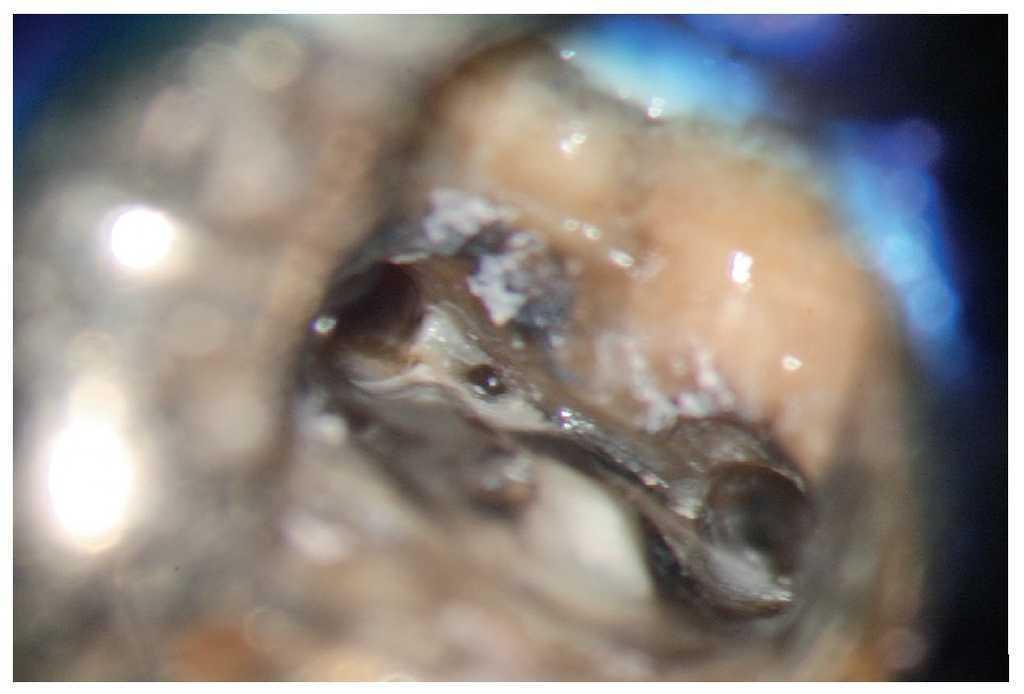

Figura 9d. Eliminación del composite alrededor del perno.

Figura 9e. Aplicación de la punta ultrasónica directamente en el segmento coronal del perno.